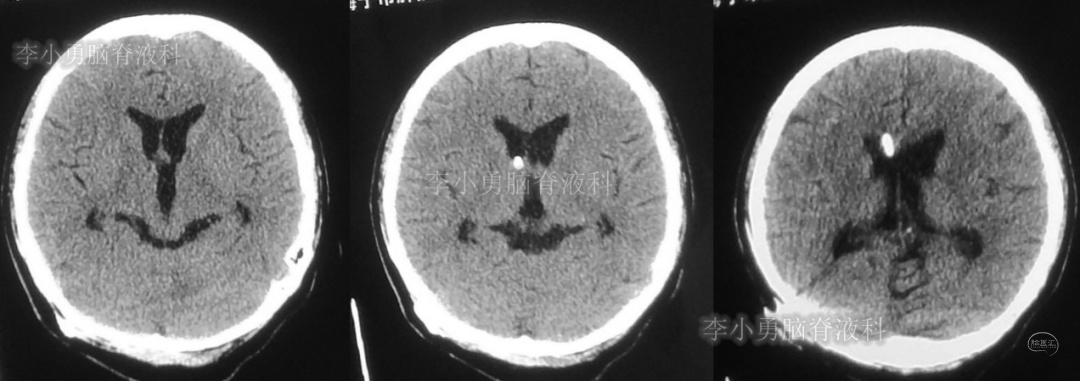

次日,即2018年11月11日,患者第2次到给予脑室腹腔分流术的医院,复查头颅CT(图-5)见脑积水仍严重。

图-5:2018年11月11日头颅CT

但第2次调压后2周,即2018年11月28日,再次到当地的第1家医院复查头颅CT(图-6)见脑积水缓解。

图-6:2018年11月28日头颅CT